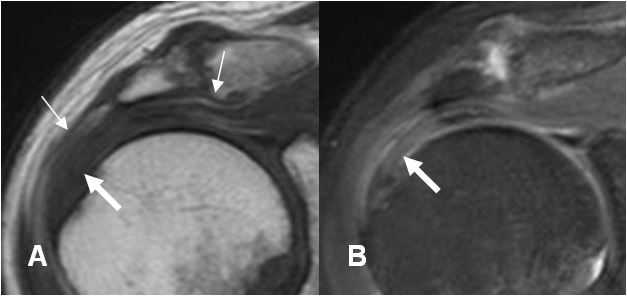

Fig 117. Ruptura parcial del supraespinoso.

A: RM coronal en T2 y B: RM coronal en STIR. Ruptura parcial del tendón supraespinoso hacia la superficie bursal (Flechas delgadas), con fibras íntegras en la superficie humeral. (Flechas gruesas).

Fig 118. Ruptura parcial del supraespinoso.

RM sagital en T2. Ruptura parcial del tendón supraespinoso en la superficie bursal (Flechas delgadas), con fibras íntegras en la superficie humeral. (Flechas gruesas).